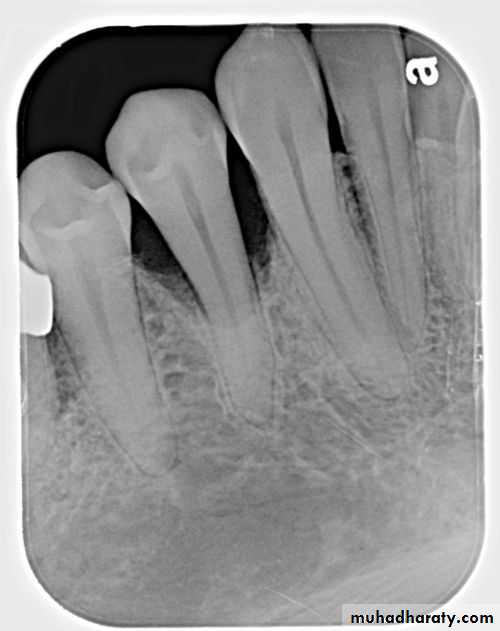

The distribution of bone loss seen on a dental image can be described as localized or generalizedLocalized: occurs in isolated area, with less than 30% of the sites involved.

Generalized: occurs evenly throughout the dental arch, with more than 30% of the sites involved.